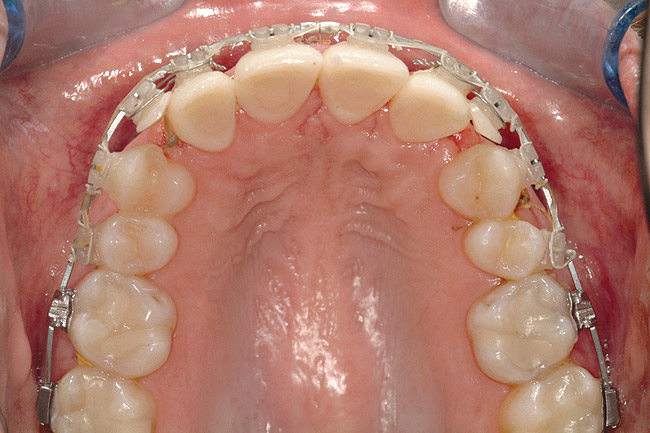

Fig 18 (through Fig 21). Note lack of alveolar development from congenitally missing Nos. 24 and 25. Surgical procedures after 5 months of orthodontic alignment included single-tooth osteotomies Nos. 6 to 11 and Nos. 21 to 28 and buccal corticotomies on all other teeth. Anchorage plate was stabilized to piriform rim.

Figure 18

Fig 20. Note lack of alveolar development from congenitally missing Nos. 24 and 25. Surgical procedures after 5 months of orthodontic alignment included single-tooth osteotomies Nos. 6 to 11 and Nos. 21 to 28 and buccal corticotomies on all other teeth. Anchorage plate was stabilized to piriform rim.

Figure 20

Fig 21 (and Fig 20). There is significant lateral dentoalveolar expansion of arches and alveoloskeletal correction in maxillary and mandibular anterior regions. Alveolar bone volume was increased in lower anterior to create optimal implant sites and establish ideal interincisal function and stability.

Figure 21